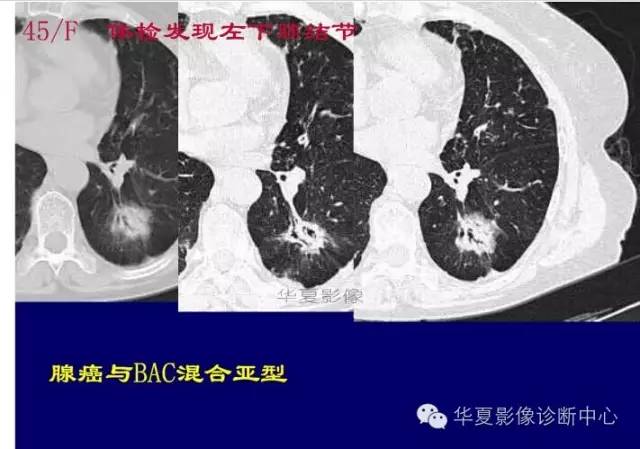

磨玻璃结节良恶性影像分析策略 混合型,边界清楚、分叶征,考虑肺癌

边界清楚,分叶征,空泡征

这一例是否GGO成分几乎没有

基本是实性的

那就按实性的分析

胸膜凹陷,分叶征